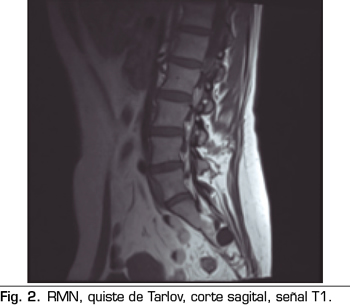

Los “quistes perineurales” o “Quistes de Tarlov” son alteraciones en la duramadre de las raíces nerviosas, que se producen más frecuentemente en la zona sacra. El diagnóstico suele ser casual mediante RMN; la incidencia es variable, debido a que el hallazgo es incidental. Habitualmente son asintomáticos, pero pueden producir radiculopatía, dolor perineal o vejiga neurógena, entre otros.

The diagnosis is usually casual by magnetic resonance. The incidence is variable, because the finding is incidental. The are usually asymptotic, but can cause radiculopathy, perineural pain or neurogenic bladder.